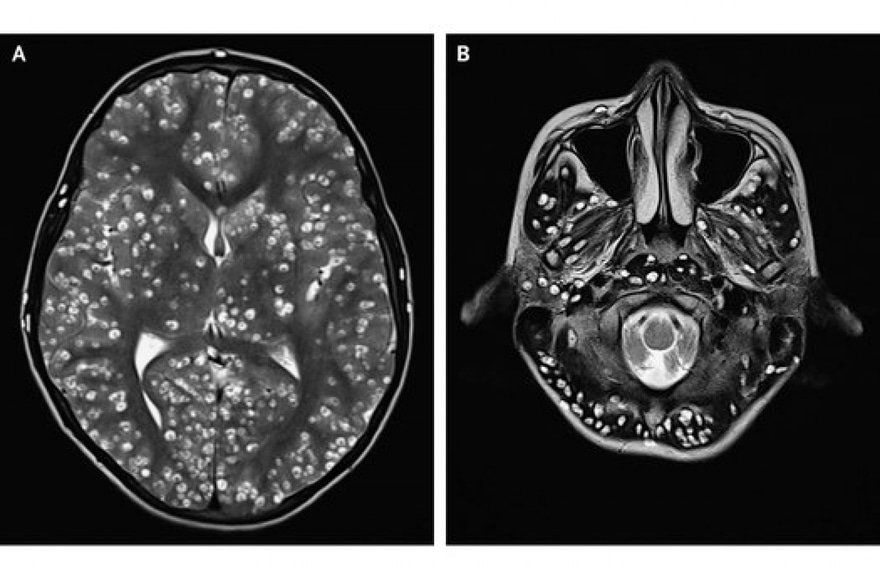

އިންޑިއާގެ ޒުވާނާގެ ސިކުނޑި ތެރޭގައި ޓޭޕްވޯމް ބިސް އަޅާފައި

އޭނާގެ އެމްއާރްއައި ސްކޭނެއް ހެދުމުން، ސިކުނޑީގައި ފާރު ހެދިފައި ހުރިކަން އެނގުނެވެ. އިތުރު ޓެސްޓްތައް ހެދުމުން، އެ ޒުވާނާ އަށް ޖެހިފައިވަނީ "ސިސްޓިސަކޯސިސް" ކަން އެނގުނެވެ. މިއީ ޓޭޕްވޯމްގެ "ޕެރަސައިޓިކް ލާވަލް ސިސްޓް" އިން ޖެހޭ އިންފެކްޝަނެކެވެ. މި ލާވާއިން ސިކުނޑި އާއި މަސްގަނޑާއި އެހެން ޓިޝޫތައް އިންފެކްޓްވެ އެވެ. އެއާ އެކު، ފިޓް ޖެހުން ފަދަ ކަންކަން ދިމާވެ އެވެ.